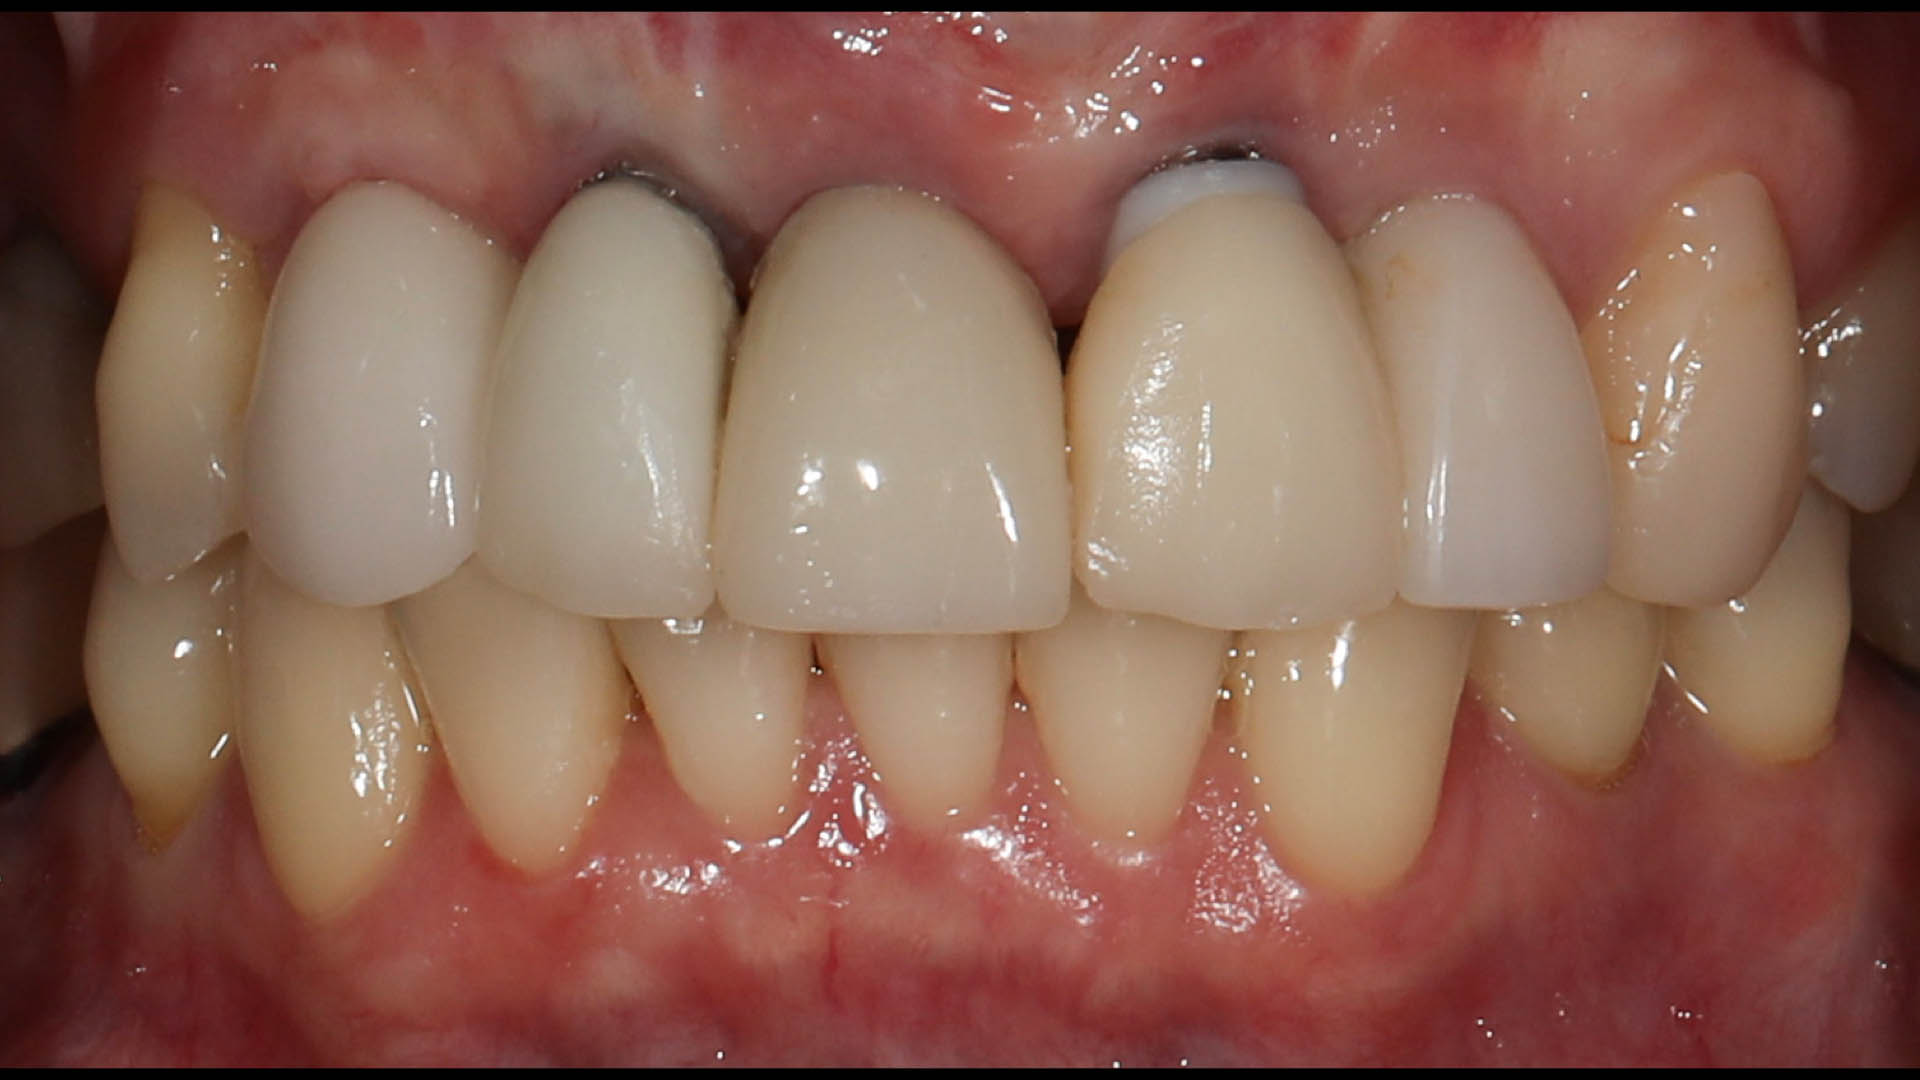

Take a glimpse into the magic of Coral Gables Dentistry through our before and after pictures. See firsthand the incredible smile makeover transformations that have brought confidence and joy to our patients.